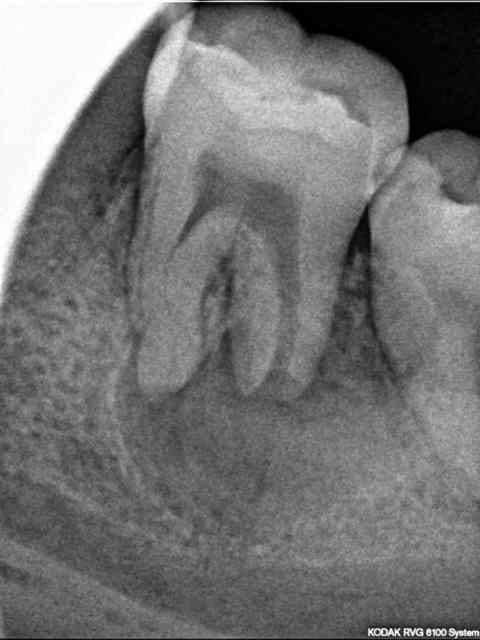

36 asymptomatique, mobilité 3. Fistule vestibulaire.

Double courbure racine mésiale. Résorption apicale racine distale et "apex" très ouvert. LIPOE > 5 mm.

Que pensez vous du trait vertical au niveau de la furcation ?